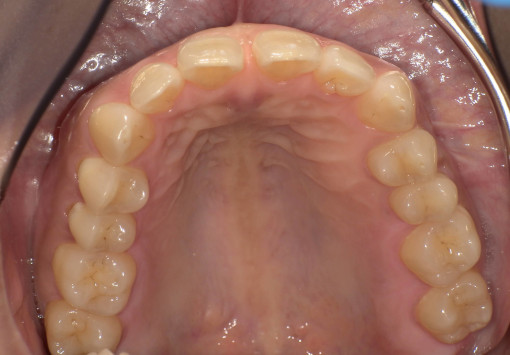

- 主訴:前歯のガタつき・上下の歯並びの不均一を改善したい。

根管治療途中の歯を治したい - 治療内容:マウスピース型矯正装置(SureSmile)による全顎矯正。

下顎1本インプラント埋入 - 治療期間:約36ヶ月

- 診断結果:

・上下顎に叢生を認め、特に上顎前歯部の位置不良が強い状態。

・噛み合わせのズレがあり、審美性・機能性の改善が必要と判断。

・抜歯を伴わないマウスピース矯正での改善が可能と診断。

歯根破折 - 治療後経過:

・前歯部の配列が整い、正中・噛み合わせが改善。経過も良好。 - 治療費用:マウスピース矯正(SureSmile):88万円税込

インプラント45万円税込

※症例により費用は前後します。

リスク・副作用:

・歯の動きに伴う痛み・違和感が数日出ることがあります。

・装着時間が不十分な場合、計画通りに歯が動かないことがあります。

・矯正後に保定装置を適切に使用しないと後戻りの可能性があります。

・虫歯・歯周病がある場合、先に治療が必要となる場合があります。